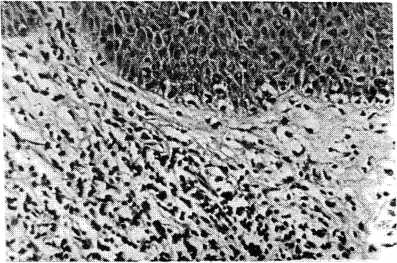

При анализе мочи отклонений от нормы не обнаружено. При гистологическом исследовании биоптата пораженной кожи задней поверхности шеи выявлено наличие выраженного инфильтрата в верхней части дермы, состоящего преимущественно из лимфоцитов, гистиоцитов и меньше из плазматических клеток и полинуклеаров. Встречались также единичные крупные клетки с гиперхромными ядрами, похожими на микозные (рис. 4). Гистологические изменения напоминали грибовидный микоз.

Рис. 4. Больной Н., 57 лет. Биоптат кожи из очага поражения на задней поверхности шеи. Окраска гематоксилин-эозином. × 160.